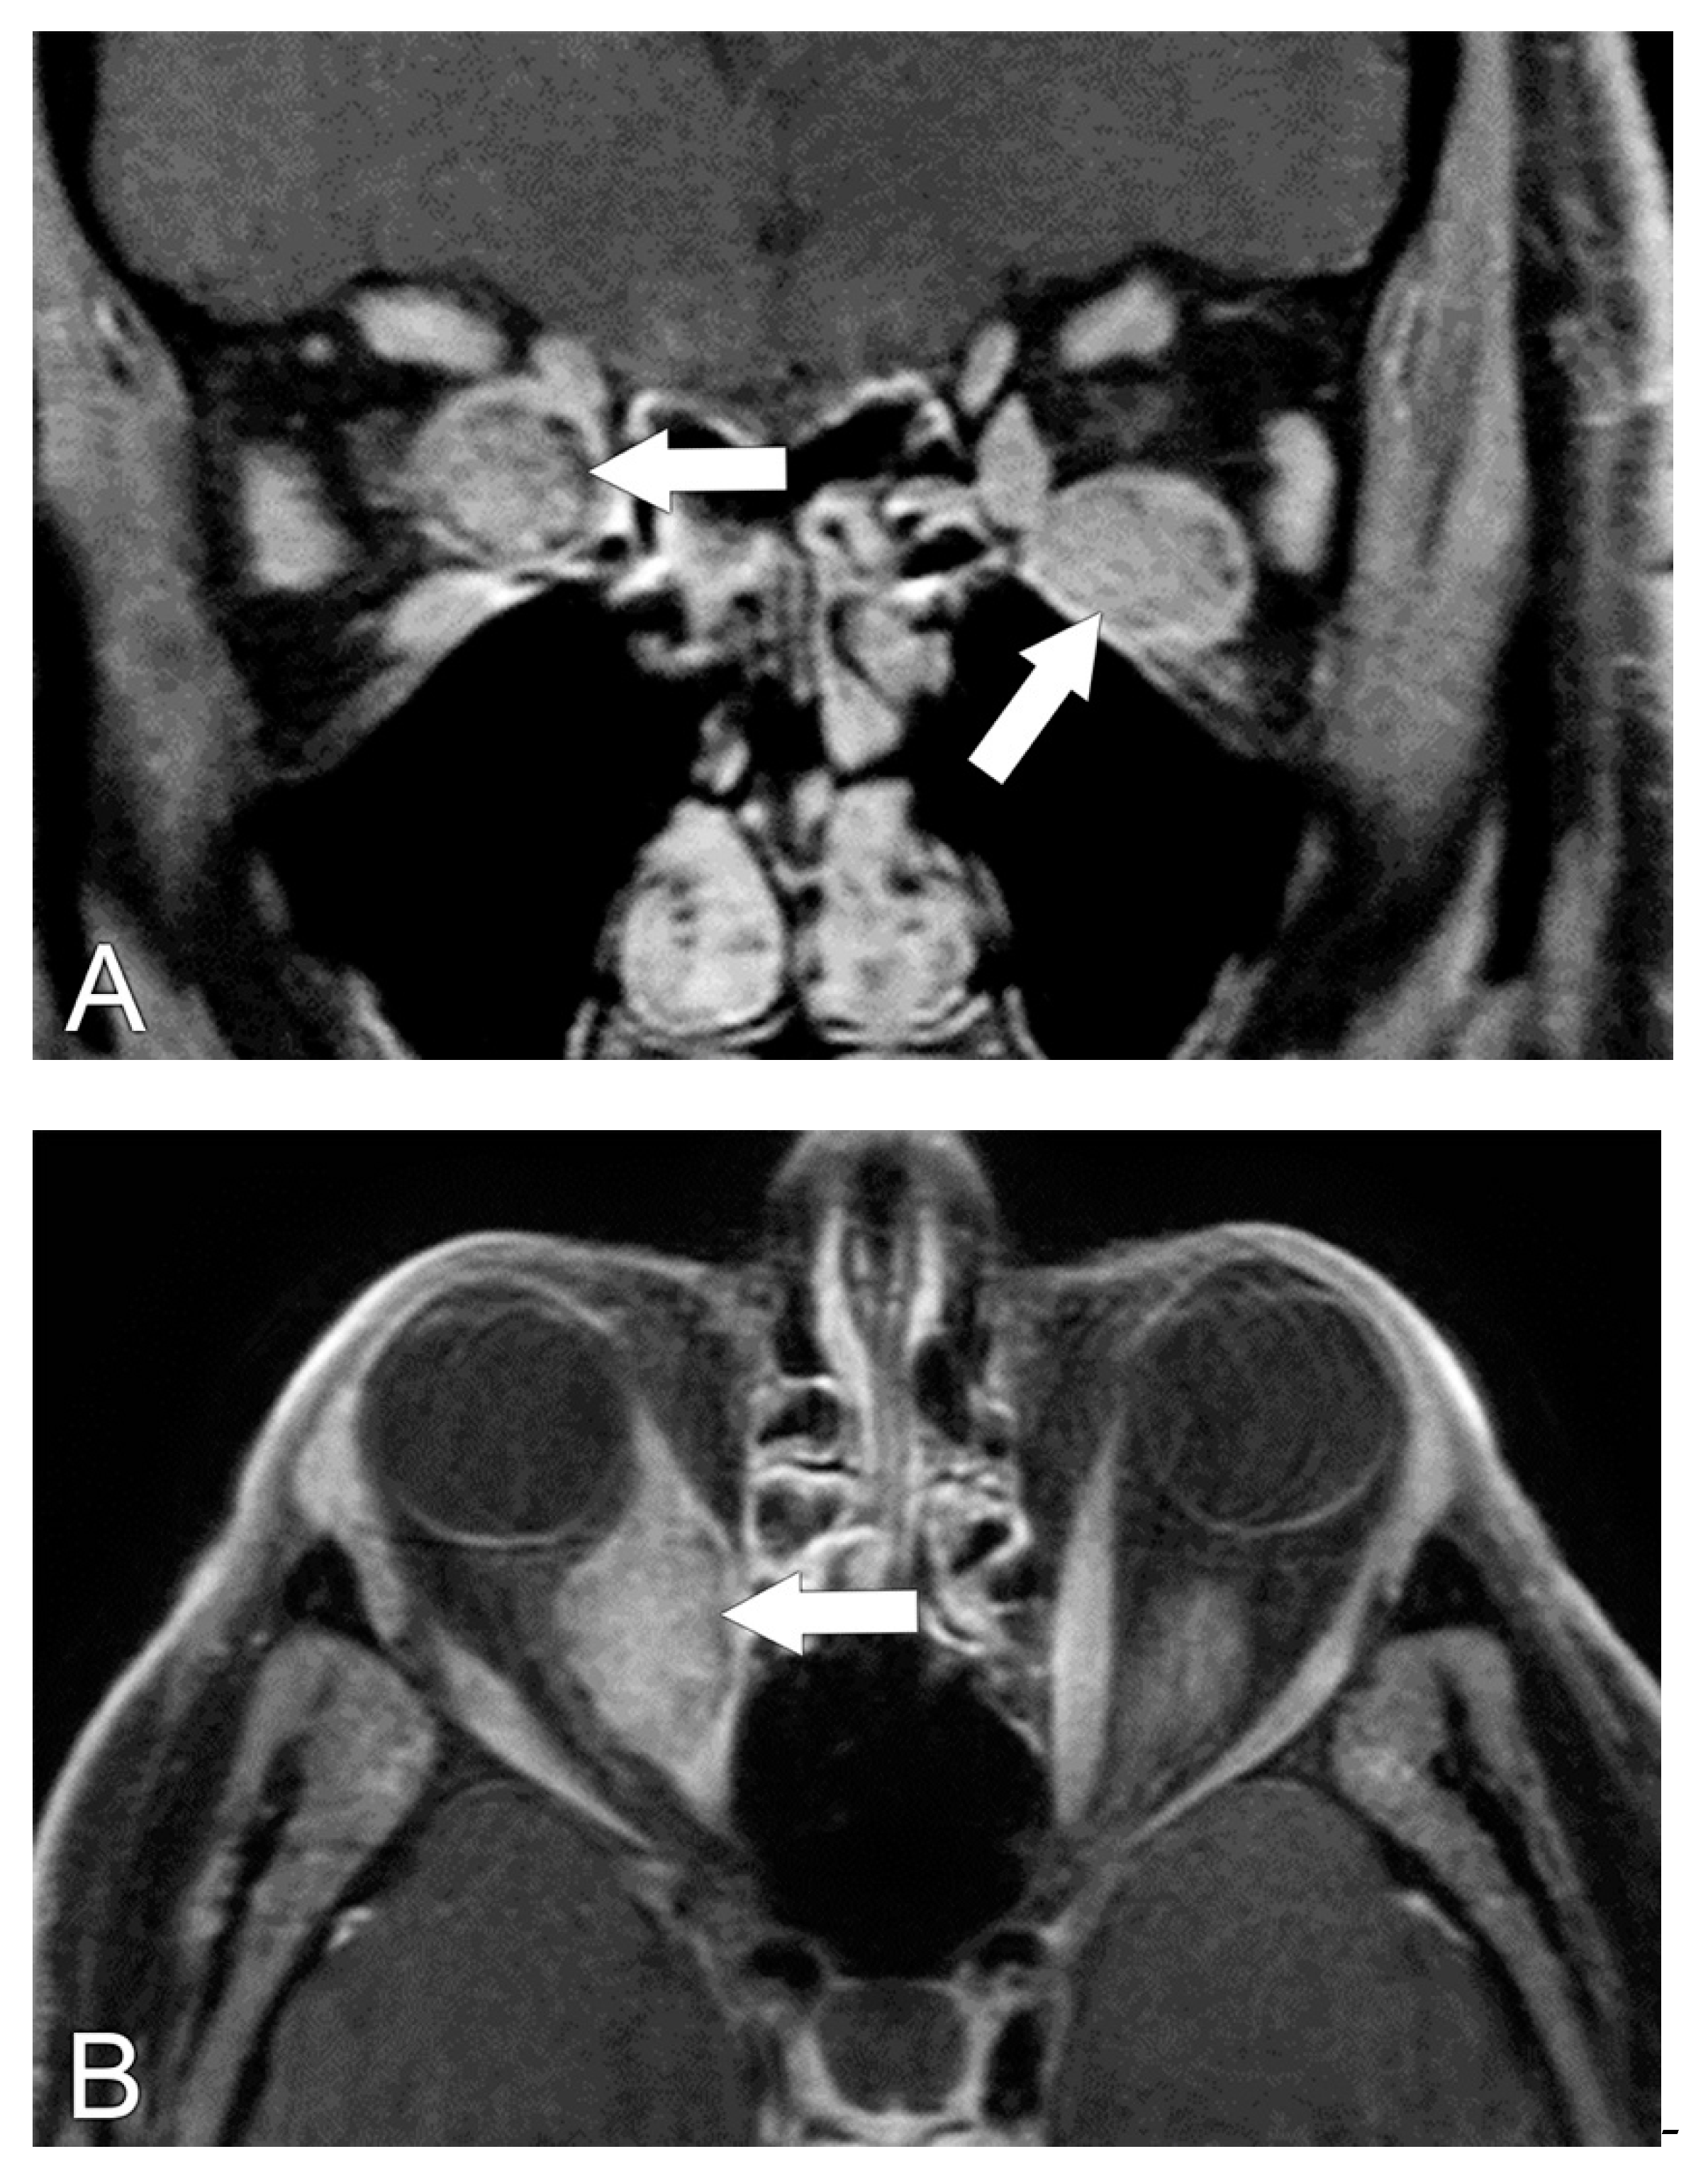

5.2. Magnetic Resonance Imaging (MRI)

5.4. Diagnosis of Compressive Optic Neuropathy (CON)

6. Radiological Differential Diagnosis